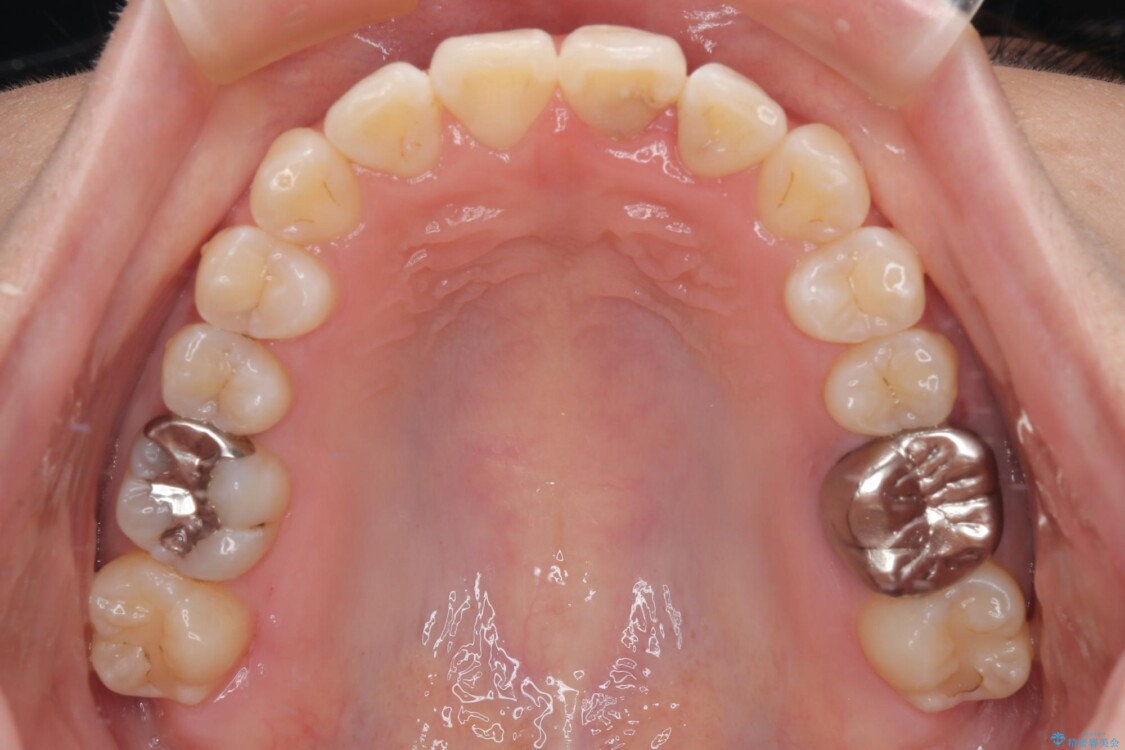

診察の結果、上下の前歯部に**叢生(そうせい/歯のガタガタ・重なり)**が認められました。

特に上の前歯にはねじれや重なりがあり、審美的にも清掃性にも影響している状態でした。

治療前

• 前歯のねじれ・ガタガタを10か月で改善!20代女性の矯正治療|クリアブラケットでむし歯になりにくい歯並びへ改善 治療前画像